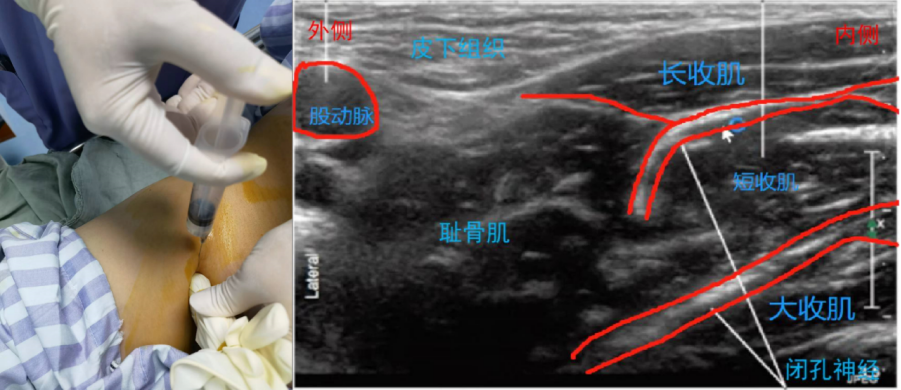

超声准备:高频探头。体位:仰卧位。

解剖关键点:腹股沟韧带下方、股动脉、大腿内侧。

扫查方法:将探头平行于腹股沟韧带置于其下方,斜轴位由外侧→内侧探查,先找到股动脉,在股动脉内侧即为耻骨肌,继续向内侧移动,可见与耻骨肌内侧相邻的三层肌肉结构,由浅入深依次是长收肌→短收肌→大收肌。闭孔神经前支在长收肌和短收肌之间,后支在短收肌和大收肌之间。

穿刺方法:平面内法,大腿外侧进针,局麻药注射于长收肌和短收肌之间和短收肌和大收肌之间。